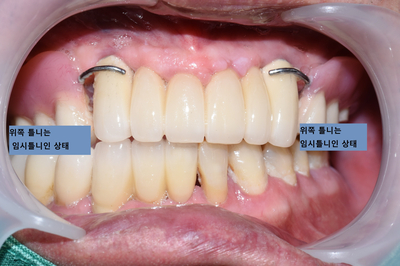

(아래 쪽은 원래 계획대로 진행되어 임플란트5개를 식립하였으며, 위 쪽은 환자가 도중에 2개의 임플란트만 심고 싶어하여 2개의 임플란트 식립)

처음과 비교했을 때 엄청난 차이를 보이죠.